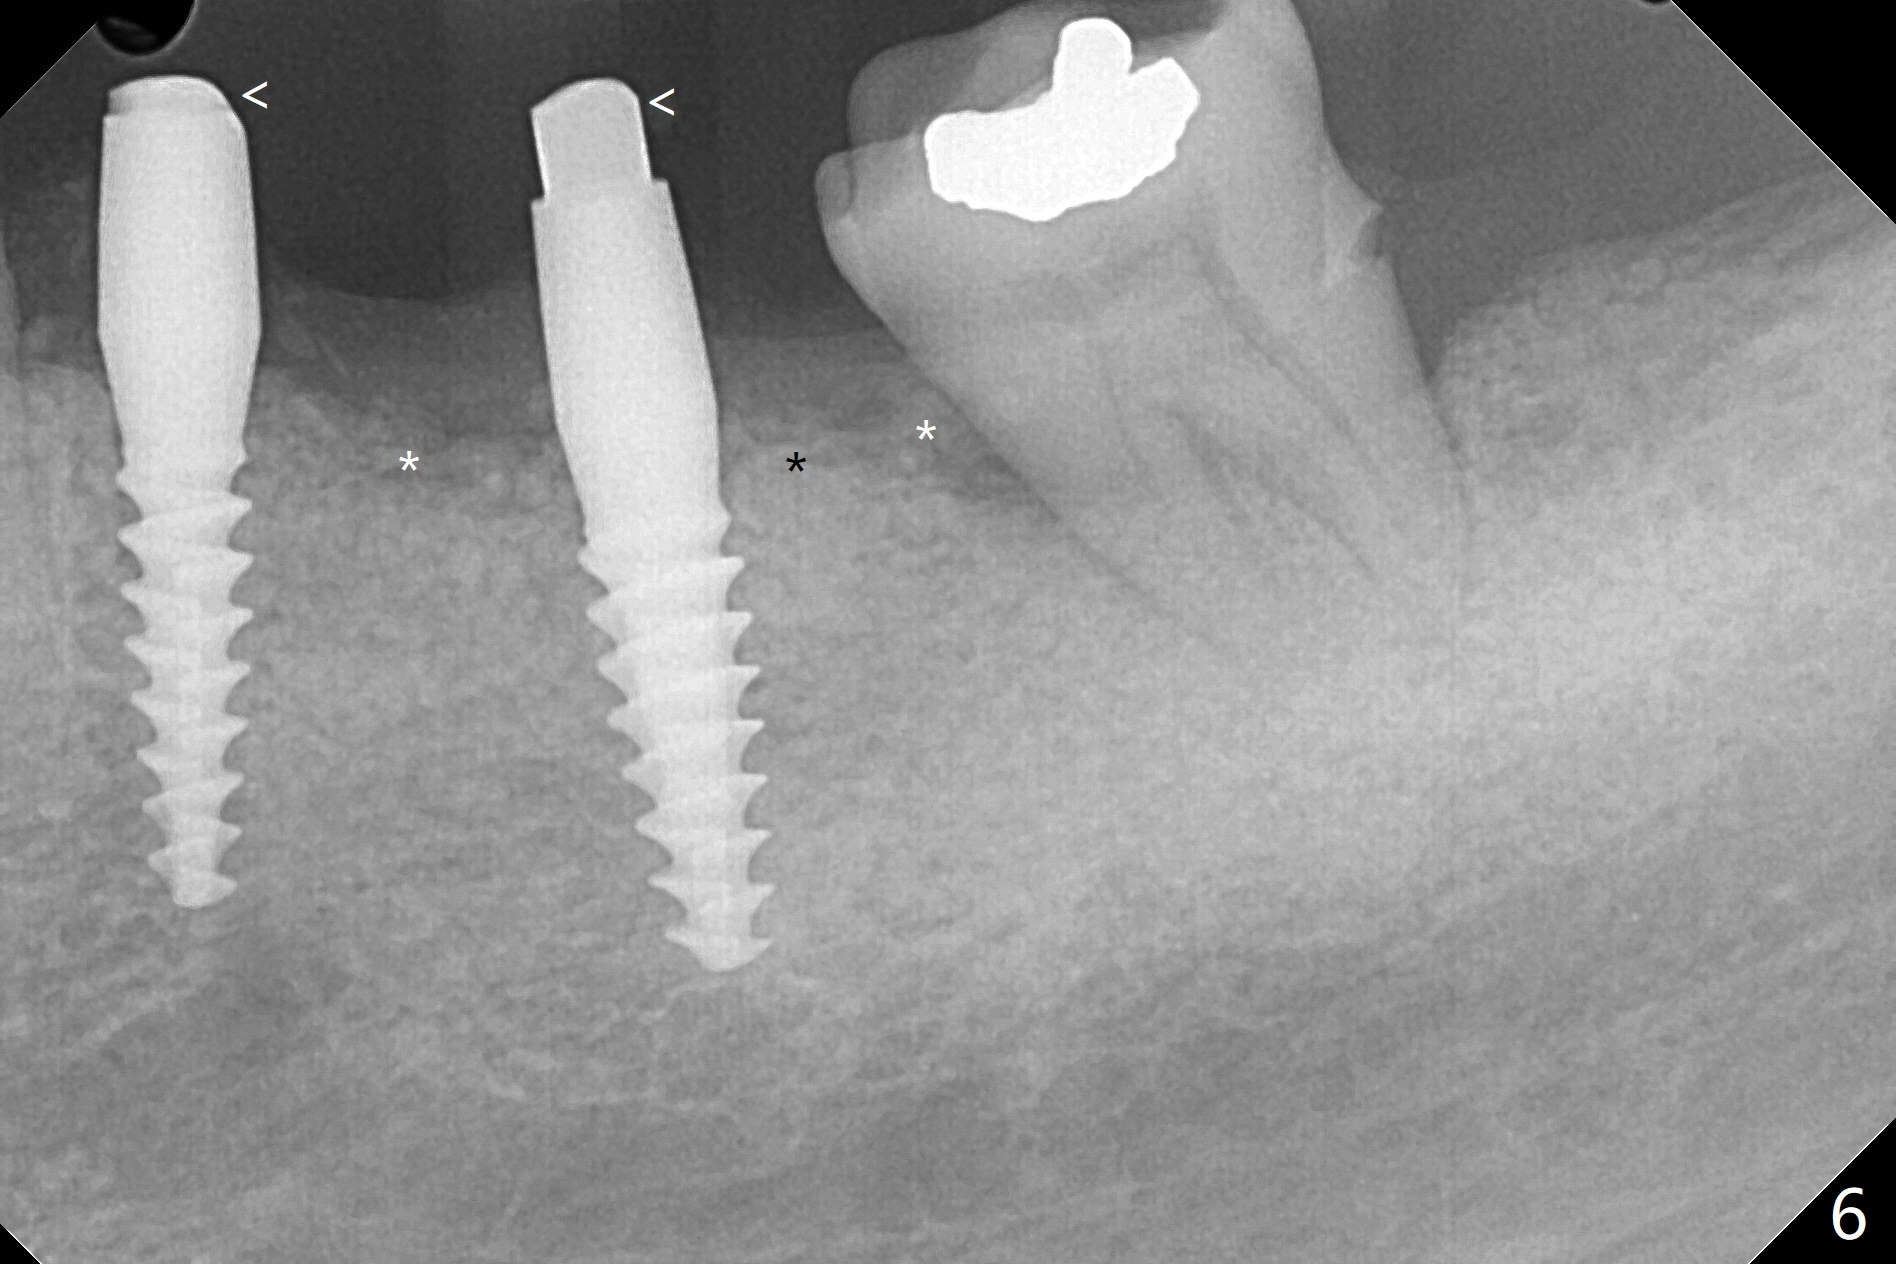

左下5,6切开,使用导板钻洞,都偏向颊侧(图一),好像牙槽嵴太狭窄,不适合做劈开术,然后改为自由手,使用Lindermann(侧方)钻头将钻洞往舌侧迁移,完成一段式植体初步钻洞(图二)以及植体植入(图三:2.5毫米(直径),根据近远中距离,植体不显得太窄)。尽管下齿槽神经阻断麻醉(开始浸润麻醉),病人疼痛明显,不敢下沉远中植体太多(图四:>),放置粘性骨块(图五,六:*)和PRF膜。缝合后,调整基台以及对合牙高度(图六: <),最后放置牙周敷料。由于植骨,术后15天植体周围形成致密的牙龈带(图七:*(gingival band))。术后一个月安置临时连体牙冠,没有任何咬合接触,主要目的防止7近中倾斜。术后三个半月临时牙冠被吞入,右侧托牙也不见了,局部牙龈健康,塞入2-0 gingival retraction cord(增加5基台长度(今后牙冠固位),图八 (>:植体螺丝刀终止地方)),取模。永久性牙冠边缘不重要,由实验室决定。清除残余粘固剂也不是很困难(图九)。